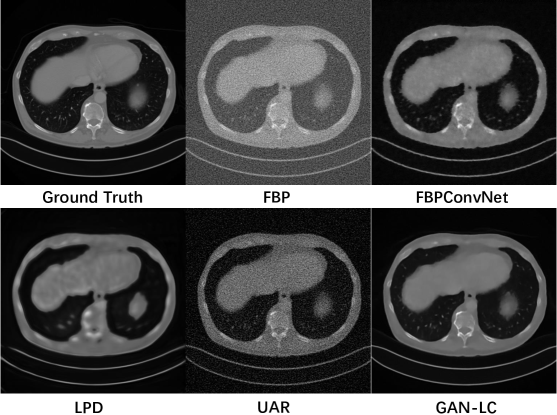

To illustrate the reconstruction performances more clearly, we also show the reconstruction results for testing images in Figure 3. We can see that our network can reconstruct the CT image with higher quality. Due to the space limit, the experimental results of different views and more visualized results are placed in our supplementary material.